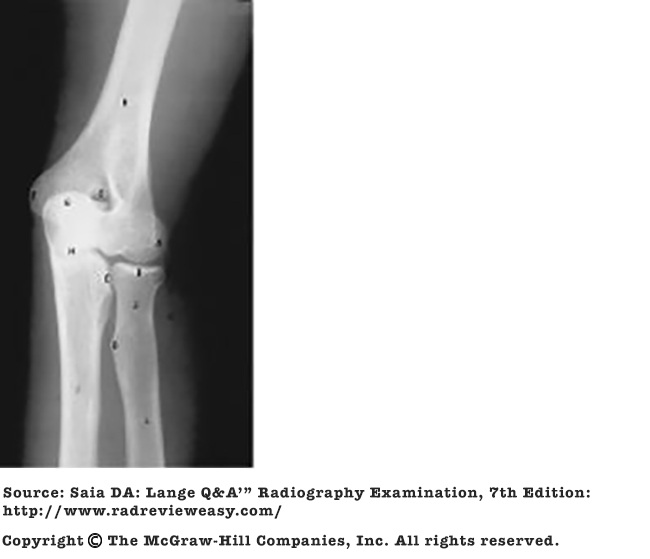

Posterior displacement of a tibial fracture would be best demonstrated in the

B lateral projection.

-A frontal projection (AP or PA) demonstrates the medial and lateral relationship of structures. A lateral projection demonstrates the anterior and posterior relationship of structures. Two views, at right angles to each other, are generally taken of most structures.